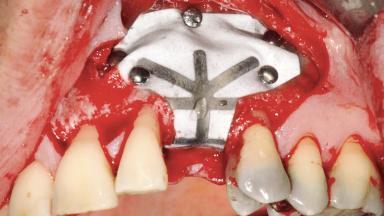

Guided Bone Regeneration (GBR) with a Particulated Autologous Graft and a ePTFE-Reinforced Membrane for Vertical Augmentation of a Single-Tooth Edentulous Space in the Esthetic Zone

A 47-year-old Caucasian woman with a single-tooth edentulous space at the site of the left maxillary canine was referred for treatment. She had undergone traumatic extraction of this impacted canine several months before referral. Her chief complaint was the dissatisfying appearance of her smile. The patient desired a stable and esthetic rehabilitation of the site. Her dental history showed no evidence of periodontal disease or bruxism. She had no systemic diseases, was not taking any medications, and did not smoke. The extraoral examination revealed a high lip line and an inadequate soft-tissue volume at the defective canine site. Large black triangles were visible between the canine and its adjacent teeth.

Bone Augmentation Staged|Vertical

Augmentation Materials Autogenous chips|Membrane